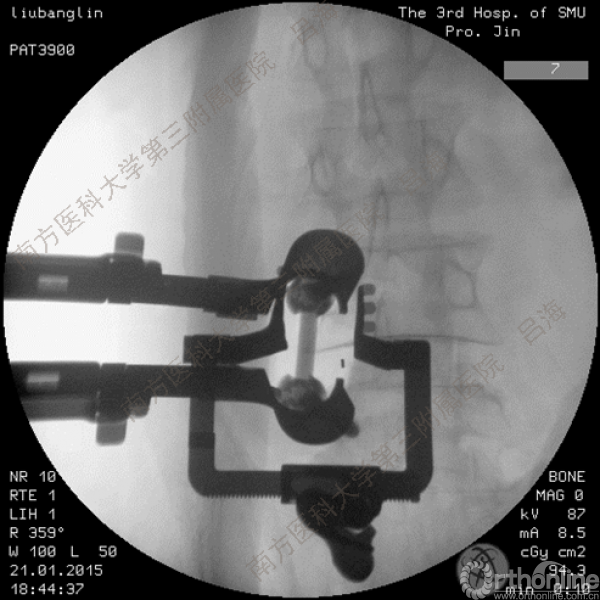

随着社会老龄化进程加快,胸腰椎退行性病变的治疗已经成为脊柱学术界的一个热点话题。MIS-TLIF手术可以治疗多种不同的胸腰椎退行性疾病,南方医科大学第三附属医院吕海教授结合病例为我们一一展示了该术式在治疗不同胸腰椎疾病时的具体手术过程。